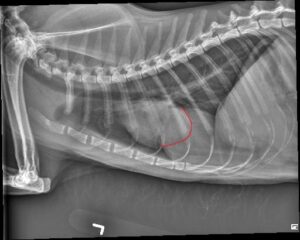

Orthogonal radiographs of the thorax are available for interpretation.

Within the cranial mediastinum, there is an ovoid, homogeneously soft tissue opaque structure which measures approximately 5.0 cm in length and extends from the second intercostal space to the fifth intercostal space along the left aspect of the cardiac silhouette. The cardiac silhouette and pulmonary vessels are normal.

The pulmonary parenchyma is normal.

The pleural space is normal.

There is mild, periarticular new bone formation at both glenohumeral joints. There is mild, multi-focal, incidental spondylosis deformans.

Within the included portion of the abdomen, the liver is mildly enlarged extending beyond the costal arch.

The ovoid soft tissue opaque structure within the cranial mediastinum may represent a malignant process (such as a thymoma) or a branchial cyst. The planned thoracic ultrasound may provide further information.

– Mild hepatomegaly is non-specific, but does raise concern for hepatic lipidosis given the reported hyporexia and anorexia. Malignancy (such as infiltrative neoplasia) cannot be excluded.

– Mild, bilateral glenohumeral degenerative joint disease.

On the annotated image the cardiac margin remains visible when superimposed with the caudal structure. This indicates that those two are not of the same opacity. Furthermore the caudal structure is slightly more radiolucent compared to the cardiac outline.